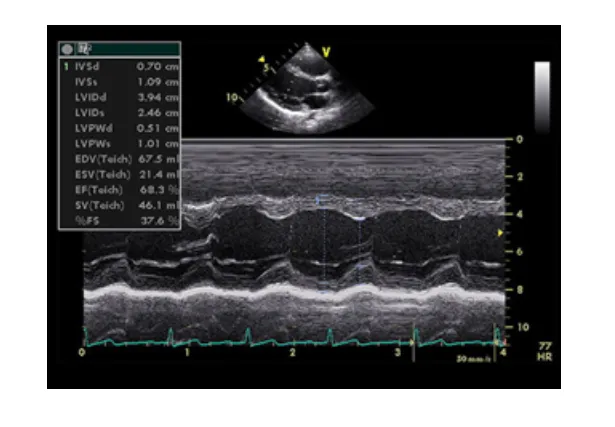

2. Siêu âm tim kiểu TM (M-mode)

Siêu âm tim kiểu TM (Time-Motion) là một kỹ thuật siêu âm tim одномерное, hiển thị hình ảnh chuyển động của các cấu trúc tim theo thời gian. Vì tim và các van tim vận động liên tục theo chu kỳ tâm thu và tâm trương, việc quét chùm tia siêu âm qua một thành phần giải phẫu của tim theo một vận tốc nhất định sẽ tạo ra hình ảnh dạng sóng, phản ánh sự thay đổi vị trí của cấu trúc đó theo thời gian.

Ưu điểm của siêu âm tim TM:

• Độ chính xác cao: Do định vị được các thời điểm trong chu chuyển tim (tâm thu, cuối tâm thu, tâm trương, cuối tâm trương), siêu âm TM cho phép đo đạc các kích thước và chức năng co bóp của tim một cách chính xác.

Các lát cắt chủ yếu trong siêu âm tim TM:

• Lát cắt trục dọc cạnh ức trái: Dựa trên hình ảnh 2D, di chuyển thanh định hướng (cursor) tới vị trí cần khảo sát để thu được hình ảnh tim mạch.

• Lát cắt trục ngang cạnh ức trái: Tương tự như lát cắt trục dọc, nhưng quan sát theo hướng khác.

Ứng dụng của siêu âm tim TM:

• Đo đường kính thất trái cuối tâm trương (LVIDd) và cuối tâm thu (LVIDs): Từ đó tính toán chức năng tâm thu thất trái (EF - Ejection Fraction).

• Đo kích thước thất phải.

• Đo độ dày của thành thất trái ở tâm trương (IVSd và LVPWd) và tâm thu (IVSs và LVPWs).